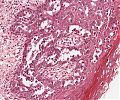

A52 Hodgkin-Lymphom

Mehrkernige Reed-Sternberg Zelle mit mit prominenten Nukleoli beim klassischen Hodgkin-Lymphom.